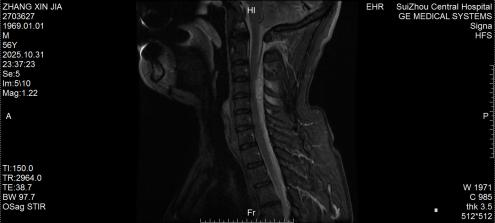

10月底的深夜,隨州市中心醫(yī)院急診醫(yī)學(xué)科來了一位特殊患者,突發(fā)劇烈頸痛伴雙手麻木,短短3小時(shí)內(nèi)肢體無力逐漸加重,連簡(jiǎn)單抬臂都難以完成。脊柱外科團(tuán)隊(duì)緊急評(píng)估后行頸椎磁共振檢查,確診為自發(fā)性頸椎椎管內(nèi)出血—— 這是今年該院救治的第5例同類患者。好在急診手術(shù)及時(shí)清除血腫、解除神經(jīng)壓迫,患者術(shù)后恢復(fù)良好,無任何后遺癥,順利出院。

圖2:術(shù)后MRI見脊髓壓迫解除

3.治療原則:一旦確診,72小時(shí)內(nèi)是手術(shù)黃金期,核心是清除血腫、解除神經(jīng)壓迫。隨州市中心醫(yī)院采用的急診減壓手術(shù),能最大程度挽救神經(jīng)功能,這也是5例患者均無后遺癥的關(guān)鍵;